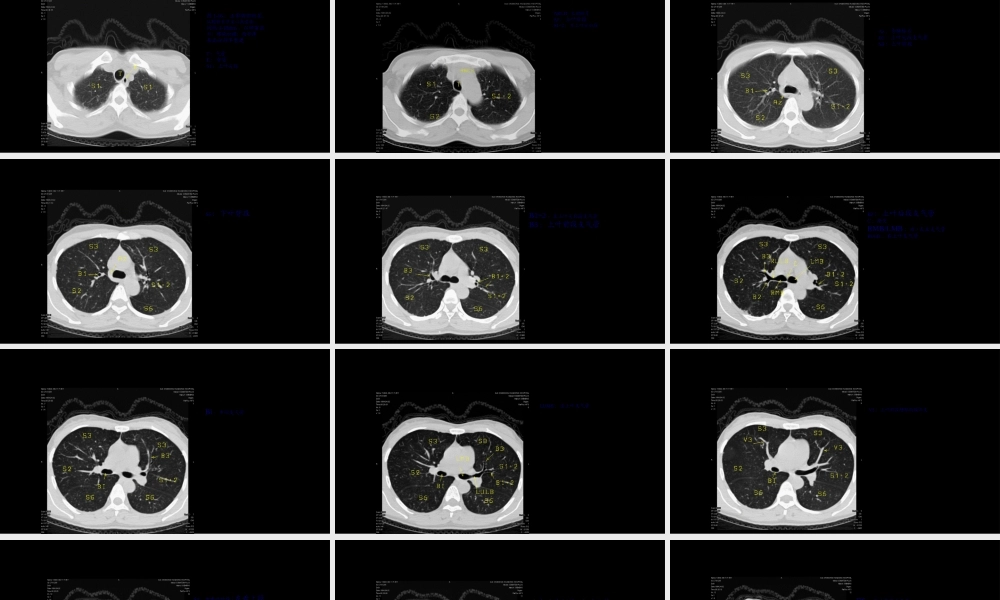

肺CT分段纵隔淋巴结分组第一页,共四十三页。图1-16:正常胸部断层,从胸锁关节至心底层面,间隔3-10mm,以肺窗显示;螺旋扫描;局部薄层高分辨率重建T:气管E:食管S1:上叶尖段图1-胸锁关节层面第二页,共四十三页。图2:主动脉弓层面ARCH:主动脉弓S2:上叶后段S1+2:左上叶尖后段第三页,共四十三页。Az:奇静脉弓B1:上叶尖段支气管S3:上叶前段图3-主肺动脉窗层面第四页,共四十三页。图4-奇静脉弓层面S6:下叶背段第五页,共四十三页。图5-近隆突层面B1+2:左上叶尖后段支气管B3:上叶前段支气管第六页,共四十三页。图6-隆突层面B2:上叶后段支气管C:隆突RMB/LMB:右/左主支气管RULB:右上叶支气管第七页,共四十三页。图7-隆突下1cm层面Bi:中间支气管第八页,共四十三页。图8-隆突下1cm层面LUMB:左上叶支气管第九页,共四十三页。图9-隆突下2cm层面V3:上叶前段静脉的段间支第十页,共四十三页。图10-隆突下2cm层面S4:右中叶外段/左舌上段第十一页,共四十三页。图11-隆突下3cm层面B4:右中叶外侧段/左舌上段支气管第十二页,共四十三页。图12-隆突下3cm层面B6:下叶背段支气管第十三页,共四十三页。图13-隆突下3cm层面第十四页,共四十三页。图14-近心底层面B5:右中叶内侧段/左舌下段支气管BS:基底干支气管MLB:中叶支气管S5:右中叶内侧段/左舌下段第十五页,共四十三页。图15-近心底层面B7+8:下叶前内段支气管第十六页,共四十三页。图16-近心底层面B7:下叶内段支气管B8:下叶前段支气管B9:下叶外段支气管B10:下叶后段支气管第十七页,共四十三页。纵隔淋巴结分组第十八页,共四十三页。〔一〕1996AJCC-UICC淋巴结分组•上纵隔淋巴结•1最上纵隔•2上气管旁•3血管前和气管后•4下气管旁〔包括奇静脉淋巴结〕•主动脉淋巴结•5主动脉下〔主-肺动脉窗〕•6主动脉旁〔升主动脉或膈神经旁〕•下纵隔淋巴结•7隆突下•8食道旁〔隆突水平以下〕•9肺韧带•N1淋巴结•10肺门•11叶间•12叶•13段•14亚段第十九页,共四十三页。•上述淋巴结中,上纵隔淋巴结〔第1-4组〕、下纵隔淋巴结〔第7-9组〕和主动脉淋巴结〔第5-6组〕属N2淋巴结•第10-14组属N1淋巴结•以纵隔胸膜反折点作为N1淋巴结、N2淋巴结的分界第二十页,共四十三页。〔二〕、1996标准淋巴结分组示意图第二十一页,共四十三页。•1996年新标准由于使用了CT上较明显的解剖结构作为分界标记,因而在横断面的CT图像上淋巴结的定位更为容易和准确。第二十二页,共四十三页...